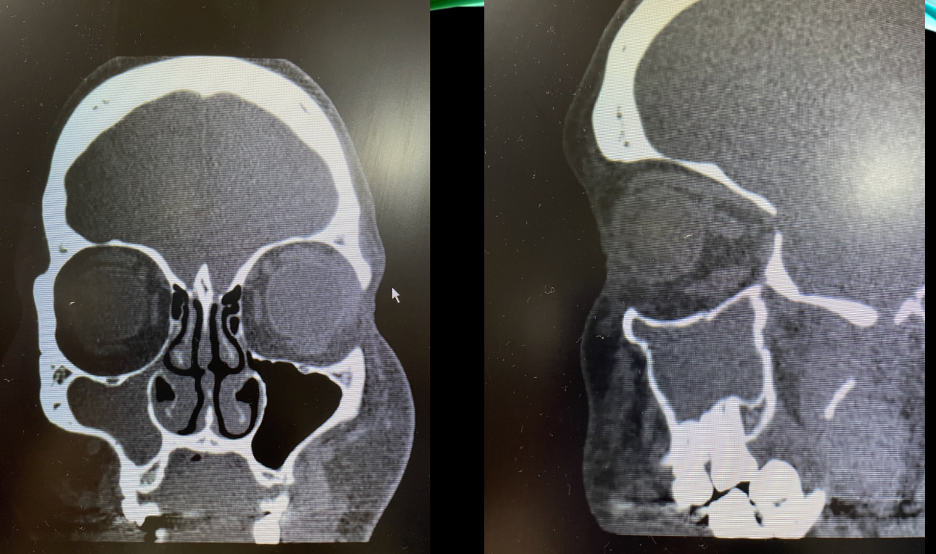

A

IMAGEN DE OCUPACIÓN PARCIAL EN SENO MAXILAR DERECHO DE UN 30% DE OCUPACIÓN. PERIFERICO, MARGINAL. CONDESVIACIÓN SEPTAL A LA DERECHA DE CONFORMACIÓN ÓSEA (PORQUE SE VE BLANCO)

SE OBSERVA HIPERTROFIA DE CORNETE INFERIOR IZQUIERDO. SUPERFICIE FESTONEADA: DEGENERACIÓN PÓLIPOIDEA.

CONCLUSIÓN: SINUSITIS MAXILOETMOIDAL BL, DESVIACIÓN SEPTAL E HIPERTROFIA DE CORNETE INFERIOR IZQUIERDO CON DEGENERACIÓN POLIPOIDEA.